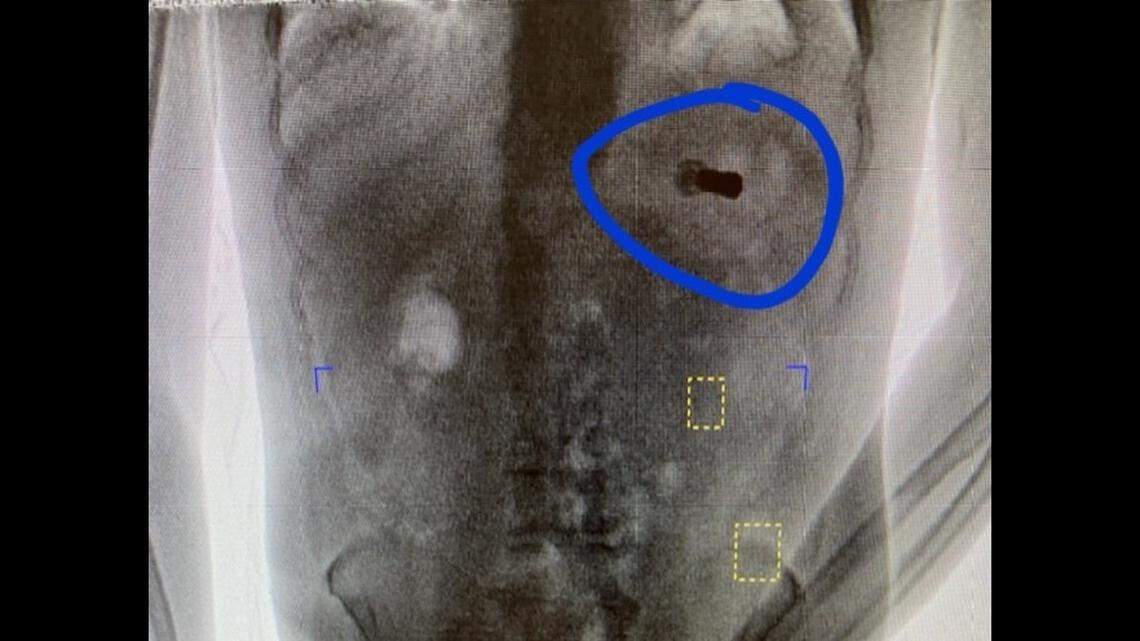

The .410 shotgun shell was discovered inside a suspect during jail intake, officials explained. Such shells “are one of the smallest gauges of shotgun ammo but pack enough punch to take down pests and small game,” according to Opticsplanet.com.

“Inmates go through our Body Scanner prior to checking in ... which catches interesting items ... like a shotgun shell,” the sheriff’s office wrote.